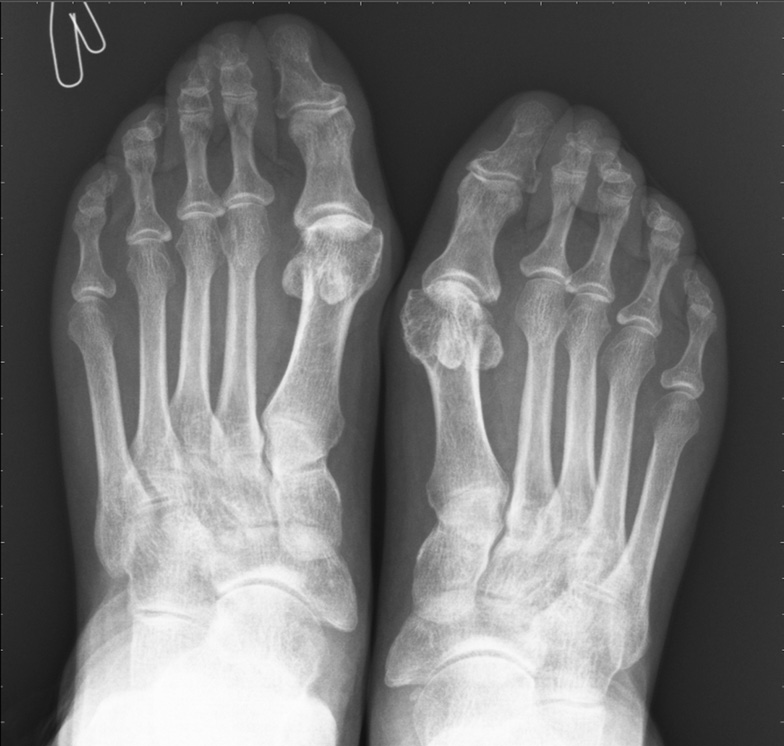

A clinical case of the onset of RA in a patient who underwent NCI was presented. Patient O., 60 years old, had NCI (confirmed by the PCR method) of moderate severity in October 2020, complicated by bilateral interstitial polysegmental pneumonia (respiratory failure of I–0 degrees). In November 2020, pains and swelling appeared in the left knee joint, followed by pains of an inflammatory nature in the right knee joint, wrist joints, and interphalangeal joints of the hands. Morning stiffness in the joints did not arrest for >30 min. She received Cartiflex at 1 sachet for 1 month and used ointments with NSAIDs without significant effect. According to laboratory data, an increased ESR up to 28 mm/h was noted. The patient was referred for hospitalization to clarify the diagnosis and treatment at the end of January 2021. Hospital: examination revealed symmetrical synovitis of the wrist joints, interphalangeal joints of the hands, left knee joint, and positive compression symptoms of the hands and feet. Pain syndrome on a visual analog scale was 8 points. The laboratory test revealed an increased level of CRP up to 12.3 mg/l, rheumatoid factor up to 89.9 IU/ml, and antibodies to ACCP over 200 IU/ml. Initial manifestations of arthritis are observed according to the X-ray data of the hands and feet (Fig. 4, 5).

Fig. 5. X-ray of the feet of patient O., 60 years old / Рис. 5. Рентгенография стоп пациентки О., 60 лет

The joint spaces in the interphalangeal joints and metatarsophalangeal joints of both feet are moderately narrowed, with moderate periarticular osteoporosis. Subluxations were not identified. A single cyst-like lucency was found in the metatarsophalangeal joints. Hallux valgus of the first toes of both feet, without erosion data (see Fig. 5).